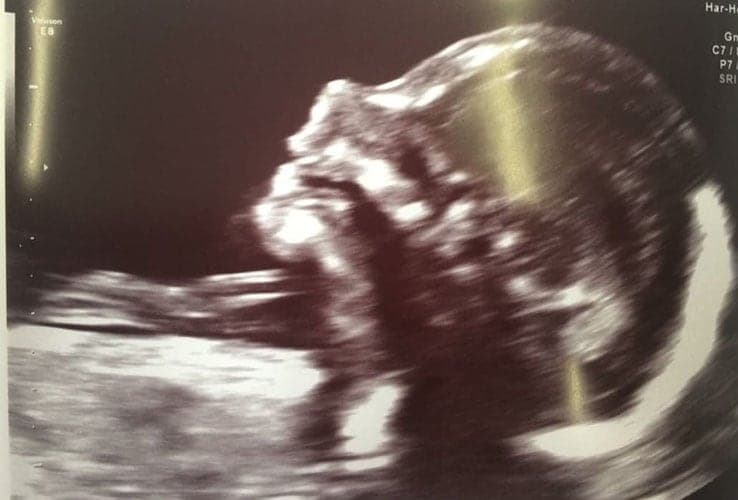

Ultraschallbilder aus dem 3. Trimester (29. bis 40. SSW)

Im dritten Trimester der Schwangerschaft ist das Baby so groß, dass es nicht mehr komplett auf ein Ultraschallbild passt. Nun kann man wunderbare 3D-Ultraschalle des Gesichts machen. In diesem Semester nehmen die Babys nochmal rasant zu und wer Glück hat, kann auf seinem Ultraschall schon erste Gesichtszüge erkennen.